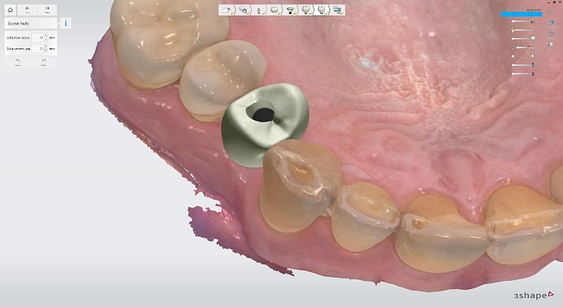

Pre-surgical planning began with acquiring high-quality diagnostic data, including TRIOS intraoral scans and CBCT imaging. The data was imported into 3Shape Implant Studio, where I designed a virtual crown for tooth 24 and planned the precise positioning of the implant, considering critical factors such as sinus proximity, adjacent roots, bone density, and the location of the bony defect.

Implant detection matches the scan body in the intraoral scan with the digital library. A colour scale is given to show the accuracy of the matching (Green is good).